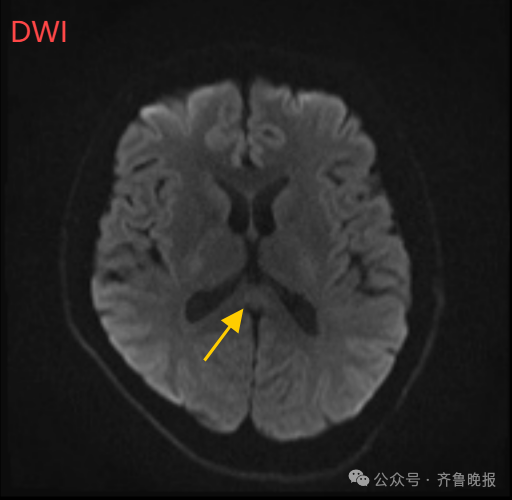

640 (5).png

经过一周治疗,小董的胼胝体压部病变明显好转